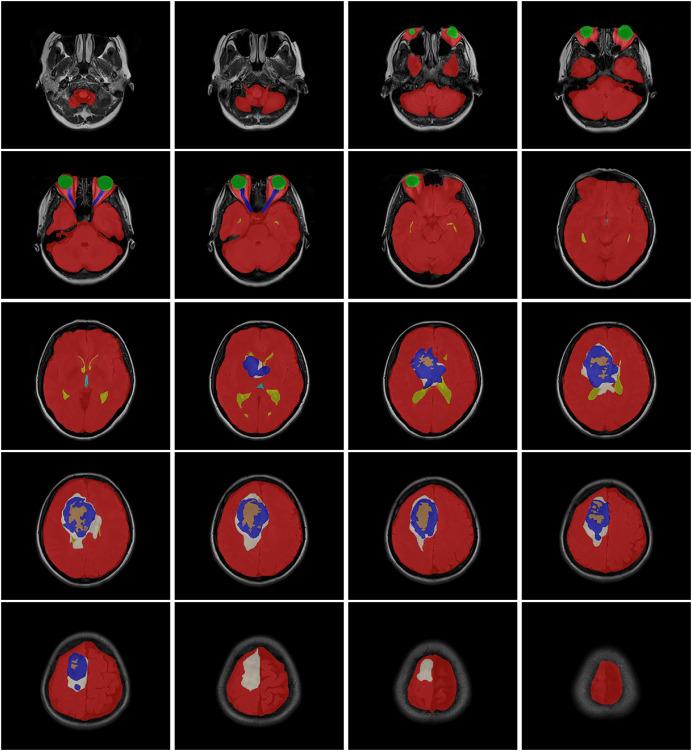

This article presents a new benchmark MRI dataset called the Gazi Brains Dataset 2020, containing MRI images of 100 patients, and introduces initial experimental results performed on this dataset in comparison with available brain MRI datasets. Furthermore, the dataset is analyzed using eight different deep learning models for high-grade glioma tumor prediction, classification, and detection tasks. Additionally, this study demonstrates the results of an explainable Artificial Intelligence (XAI) approach applied to the trained models. To demonstrate the utility of the proposed dataset, different deep learning models were applied to the problem, and these models were tested on various data and models applied for various tasks such as region of interest extraction, whole tumor segmentation, prediction, detection, and classification with accuracy, precision, recall, and F1-score. The experimental results indicate that the dataset is highly effective for multiple purposes, and the models reached significant results with successful F1-scores ranging between 93.2% and 96.4%. ROI and whole tumor segmentations were successfully performed and compared with seven algorithms with accuracies of 87.61% and 97.18%. The Grad-CAM model also demonstrated satisfactory accuracy across the tests that were conducted. Moreover, this study explores the application of XAI to the trained models, providing interpretability and insights into the decision-making processes. The findings signify that this dataset holds significant potential for various future research directions, including age estimation, gender detection, causal inference with XAI, and disease-related survival analysis.

本文介绍了一个名为2020年加济大脑数据集的新的基准MRI数据集,其中包含100名患者的MRI图像,并介绍了与现有脑MRI数据集相比在该数据集上进行的初步实验结果。此外,使用八种不同的深度学习模型对该数据集进行分析,以完成高级别胶质瘤肿瘤的预测、分类和检测任务。此外,本研究展示了将可解释人工智能(XAI)方法应用于训练模型的结果。为了证明所提出数据集的实用性,将不同的深度学习模型应用于该问题,并在各种数据和模型上对这些模型进行测试,这些数据和模型用于各种任务,如感兴趣区域提取、全肿瘤分割、预测、检测和分类,并计算其准确率、精确率、召回率和F1分数。实验结果表明,该数据集在多个方面都非常有效,模型取得了显著成果,F1分数成功达到93.2%至96.4%。成功进行了感兴趣区域和全肿瘤分割,并与七种算法进行了比较,准确率分别为87.61%和97.18%。Grad-CAM模型在进行的测试中也表现出令人满意的准确率。此外,本研究探索了将XAI应用于训练模型,为决策过程提供了可解释性和见解。研究结果表明,该数据集在包括年龄估计、性别检测、利用XAI进行因果推断以及疾病相关生存分析等各种未来研究方向上具有巨大潜力。